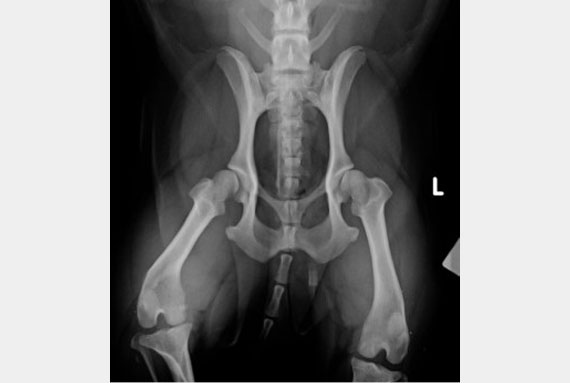

Radiology

We have a digital x-ray for your pet’s body. Digital x- ray allows quick turnaround to see images resulting in less sedation or GA time. The image quality is superior to ensure accurate interpretation.